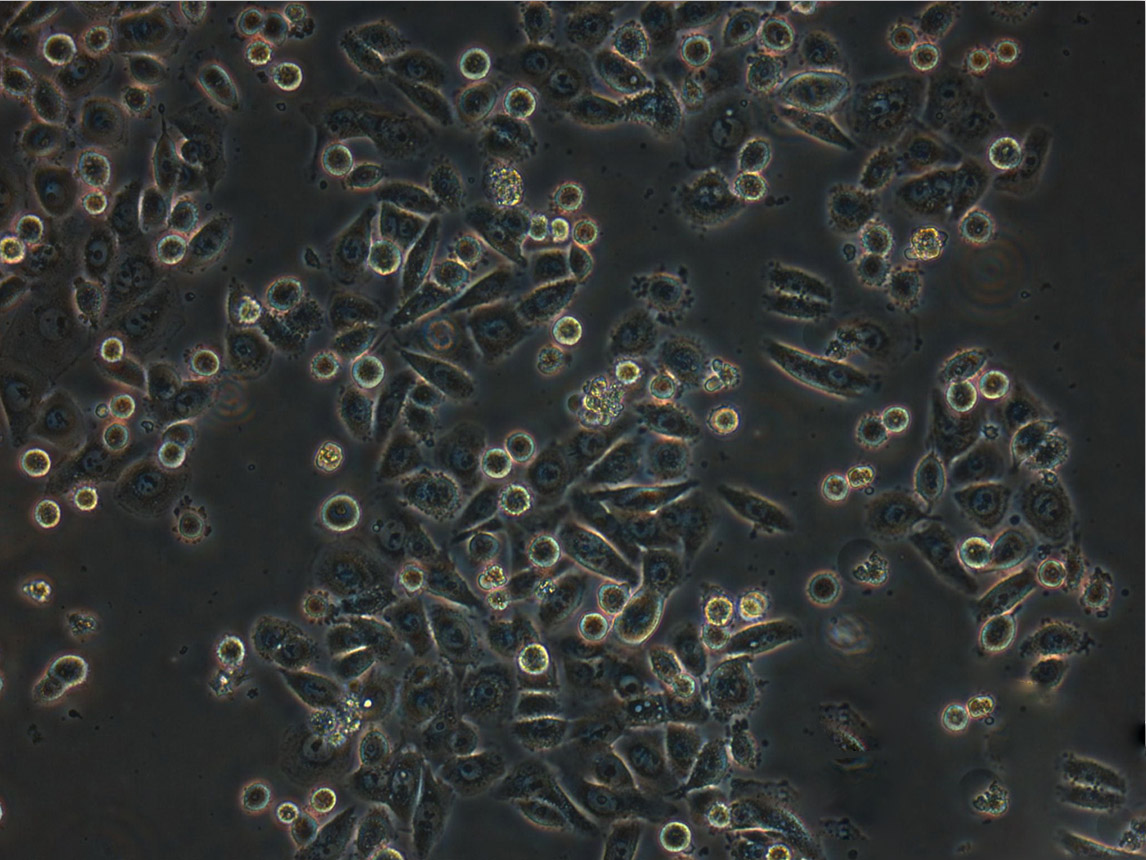

NCM356:结直肠腺癌复苏细胞(提供STR鉴定图谱)

细胞生长:贴壁

细胞形态:上皮细胞样

细胞生长特性:贴壁生长